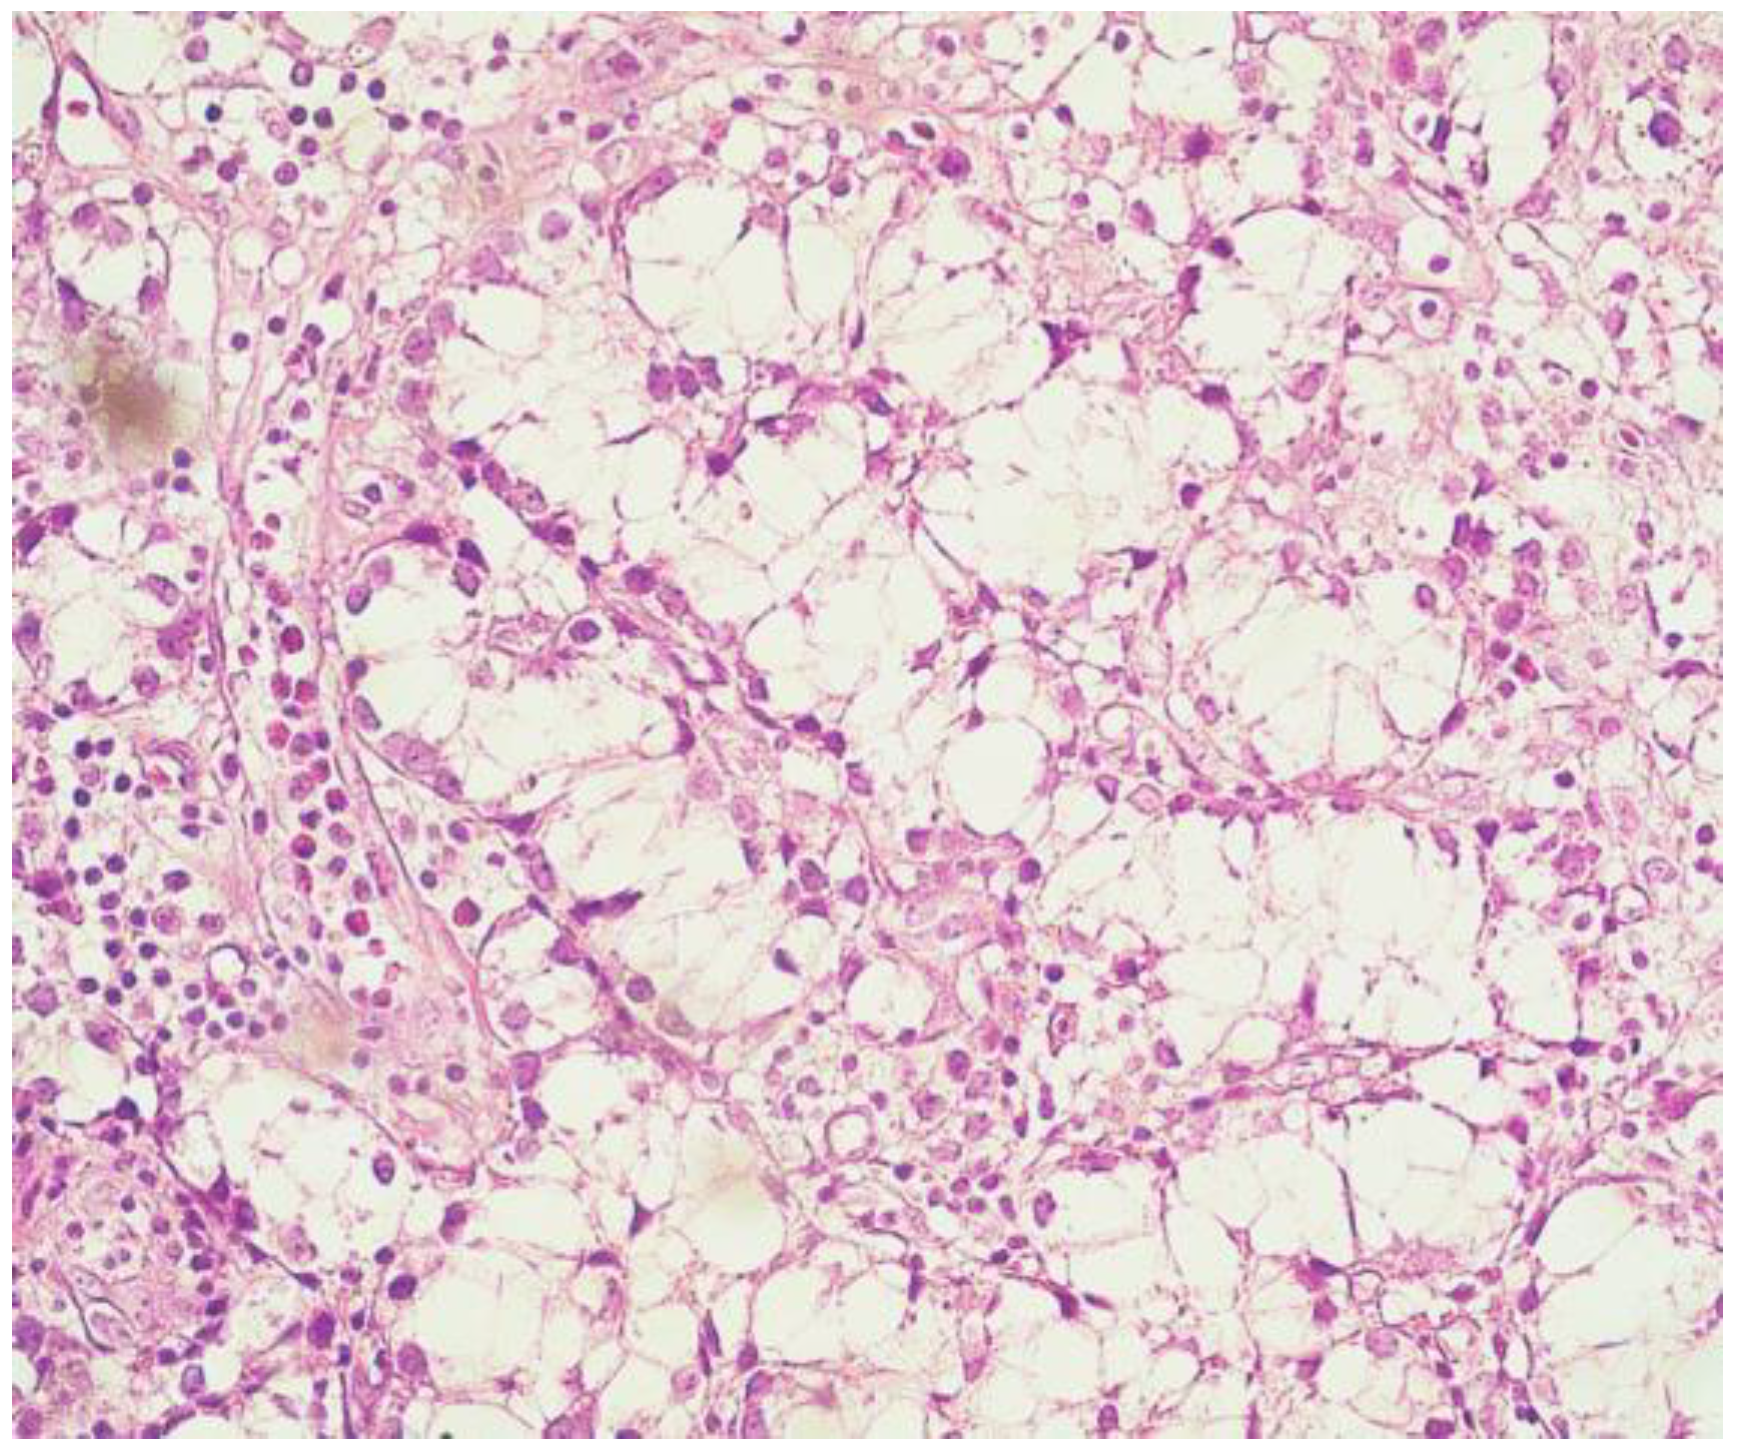

4. Diagnosis